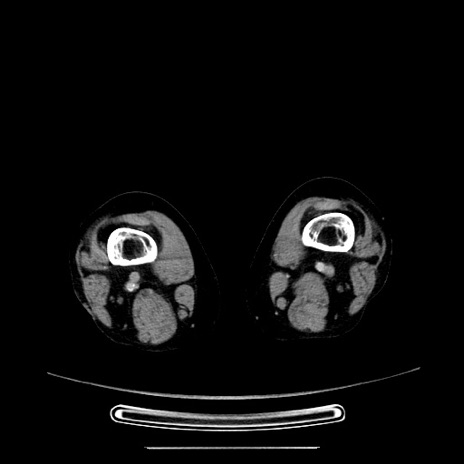

症例5(横断像)

【症例】70歳代女性

【主訴】お腹が張る

【現病歴】1週間くらい前から腹部膨満の自覚あり。昨日夜から増悪したため、本日救急外来受診。

【身体所見】意識清明、BT 36.5℃、BP 165/106mmHg、HR 80bpm、SpO2 98%、腹部:膨満、軟、自発痛・圧痛なし、触診にて不快感あり、腸蠕動音:減弱

【データ】WBC 12600、CRP 1.04